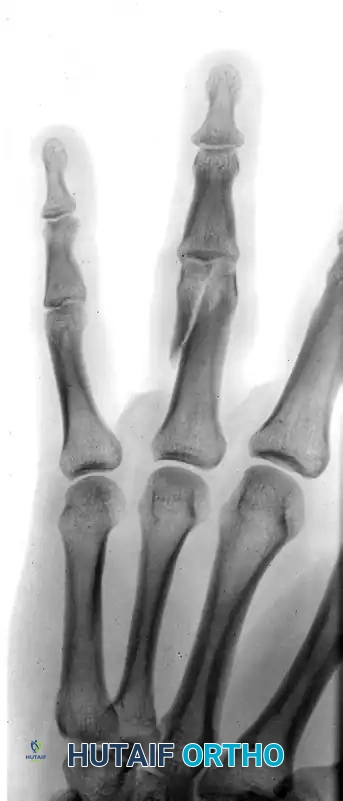

The following radiographs demonstrate a complex, three-part displaced intra-articular fracture of the proximal phalanx in a 27-year-old man. The articular surface is significantly disrupted, necessitating open reduction.

FIGURE 67-41 A: Preoperative anteroposterior radiograph demonstrating the intra-articular split.

FIGURE 67-41 B: Preoperative oblique radiograph highlighting the displacement and articular step-off.

FIGURE 67-41 C: Preoperative lateral radiograph showing the volar subluxation tendency.